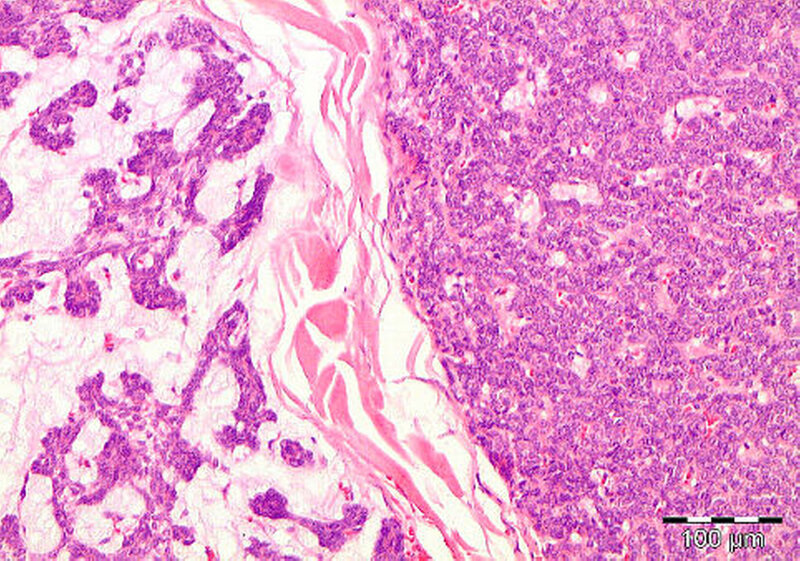

Der histopathologische Befund bestätigte den Verdacht eines pleomorphen Adenoms mit kapselartiger Begrenzung zum umgebenden, strukturell unauffälligem Speicheldrüsenparenchym der linken Glandula parotis (Abbildungen 5 und 6).

Das pleomorphe Adenom ist ein gutartiger Mischtumor der Speicheldrüsen, der sich durch seine strukturelle Pleomorphie auszeichnet. So erscheinen im histopathologischen Bild epitheliale und myoepitheliale Zellen, vermischt mit mucoiden, myxoiden und chondroiden Komponenten [Jain et al., 2015].

Bei fehlender vollständiger Kapsel ist eine klare Abgrenzung zum angrenzenden Gewebe schwierig. Das pleomorphe Adenom ist von gesundem Speicheldrüsengewebe umgeben, welches durch sein Wachstum komprimiert wird [McGurk et al., 1996; Zbären und Stauffer, 2007].